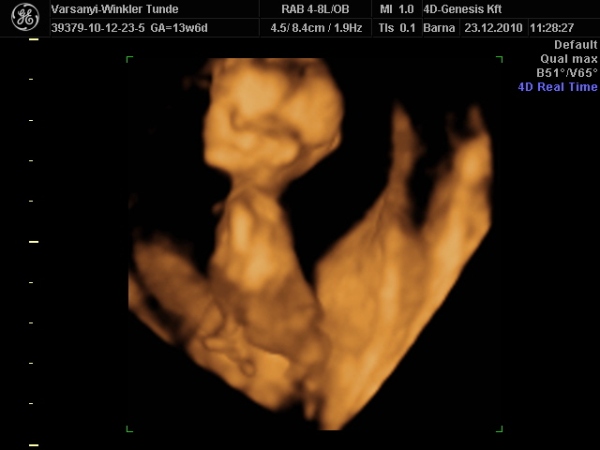

Bár tegnap a dokor bácsi azt mondta, hogy azért lassan vissza kellene vennem a lendületből, mert nem lesz jó vége. Manócska jól van, de tegnap nem tudtuk megnézni. Hasi uh-val próbálkozott, de pont úgy fordult, hogy csak a nagy kobakját láttuk

Gondolta, ha arra van a feje, akkor lentről lehet látni valamit a neméből.

Be is terpesztett rendesen, mint egy kis utcalány

Természetesen lánynak is látszott, bár azt mondta, hogy még ne éljük bele magunkat. A férjem le is tört egy kicsit, de nem vallotta volna be.Holnap reggel megyek AFP-re.